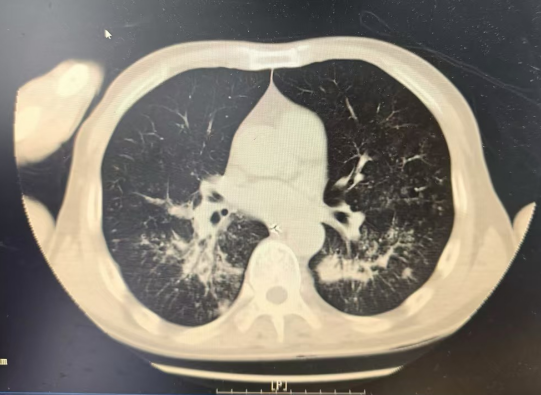

重癥醫(yī)學(xué)科林捷主任帶領(lǐng)科室醫(yī)護(hù)團(tuán)隊(duì)立即給予呼吸循環(huán)支持、容量管理、臟器功能保護(hù)等治療,并進(jìn)行床旁重癥超聲檢查評(píng)估心肺功能等。抽血結(jié)果顯示:血?dú)夥治鎏崾狙鹾现笖?shù)僅114mmHg(低于300提示存在呼吸衰竭),血乳酸3.49mmoL/L,白細(xì)胞高達(dá)20.9×109/L 。CT 提示:雙肺大片炎癥伴肺水腫。

治療前CT影像